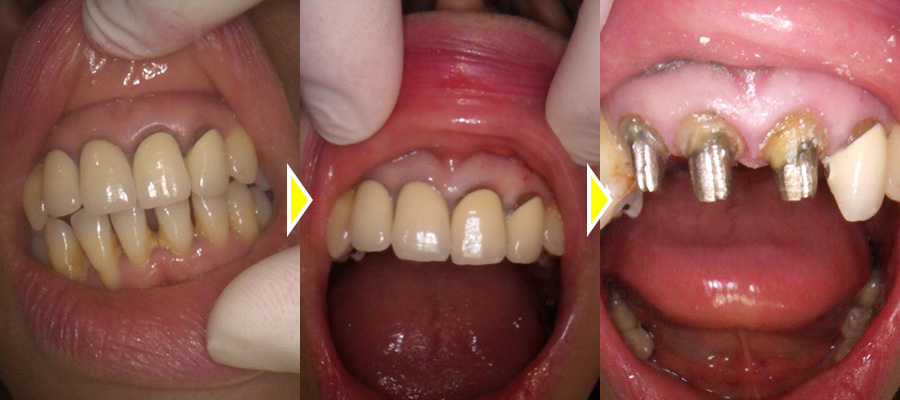

左上2番目の歯根感染で抜歯をインプラントで修復した症例

こちらの患者さまは、前歯が何もしなくても痛みがあるとの主訴で来院されました。

レントゲンでの検査の結果、左上2番目の歯の根に感染が起こっており、膿が溜まっていたため痛みが出ていたと診断しました。

CT写真にて確認したところ、膿がかなり大きく、治療しても完治が難しいため患者さまと相談し、成功率が高いインプラントでの治療をご希望されました。

また、過去に他院で治療をした他の前歯の見た目も気になっていたため、審美的に綺麗にしたいとの事であわせて前歯クラウンのやり直しもご希望されました。

前歯のクラウン除去、中の土台の型取り、仮歯の作成をまず行い、次に左上2番の抜歯、インプラントの埋入、骨造成仮歯へまでを1回のオペで行いました。